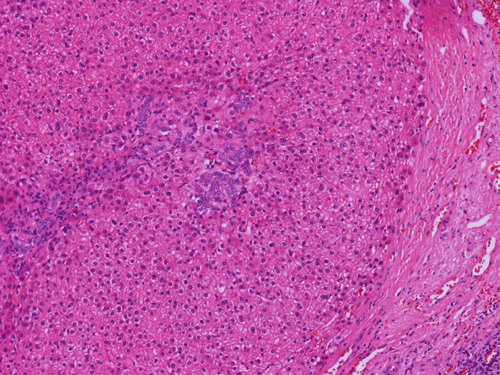

Histologically, the grossly notable nodules correspond to islands of cells separated by dense fibrous tissue  (Panel B). On medium magnification, the islands of cells have smooth, pushing margins (Panel C). The cells are quite similar to normal hepatocytes except that these islands do not have the general architecture of normal liver (Panel D). The liver plate varies from one to three cell thick is well demonstrated by reticulin stain (Panel I). In some areas there are some entrapped ductular structure consistent with bile ductules (Panel E and F) and they are well demonstrated by immunohistochemistry for cytokeratin 7 (Panel J and K). Most of these ductules are found around the fibrous scar or septa or at the edge of the nodules. Many abnormally large blood vessels are also noted and many of them are seen in the fibrous central scar (Panel G and H).

The histopathologic triad of FNH is bland hepatocytes without abnormal architecture, preserved reticulin network, the presence of bile ductules, central scar with fine fibrous septa radiating out, and the presence of large and abnormal blood vessels surrounded by a zone of connective tissue.

The central scar is composed of dense collagenous fibrous tissue with a variable number of tortuous thick-walled arteries. Fibromascular hyperplasia and myxoid degeneration are often found in these vessels.The areas away from the scaring portion and the fibrotic septa would look like normal liver at scanning magnifications. The key feature at low magnification is that no normal portal triads, no central vein or portal arteries are present. Instead, bile ductules are usually evident and often associated with chronic inflammatory cell infiltration.

Histologically, the cells in FNH are  almost identical to the normal hepatocytes surrounding hepatocytes. The reticulin network is preserved and the liver plate varies from one to three cells thick. The cells in FNA  may possess increased cytoplasmic glycogen content, focal steatosis, bile stasis, lipofuscin, iron pigment, copper deposits and Mallory bodies 4.   The central scar is composed of dense collagenous fibrous tissue with a variable number of tortuous thick-walled arteries. Fibromascular hyperplasia and myxoid degeneration are often found in these vessels.